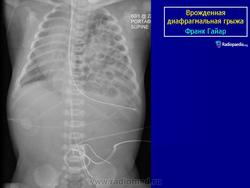

Врожденная диафрагмальиая грыжа встречается с частотой 1 на 2000 рождений. Многие из детей с ВДГ и многоводием у матери умирают после рождения, так как желудок пролабирует в грудную полость и имеет место значительное недоразвитие легкого. После рождения у ребенка возникают трудности в прохождении воздуха в легкие, так как нет сокращения диафрагмы и, кроме того, сдавление усугубляется гиперпневмотозом кишечника. Наблюдается цианоз, гипоксия, алкалоз. У таких детей уменьшен живот в размерах (ладьевидный живот), некоторая асимметрия грудной клетки, смещение тонов сердца, отсутствие дыхания на стороне грыжи.

Диагноз может быть установлен пренатально при ультразвуковом исследовании, после рождения при рентгенологическом. По литературным данным, от 5 до 25% диафрагмальных грыж выявляются от 1 месяца до старости.